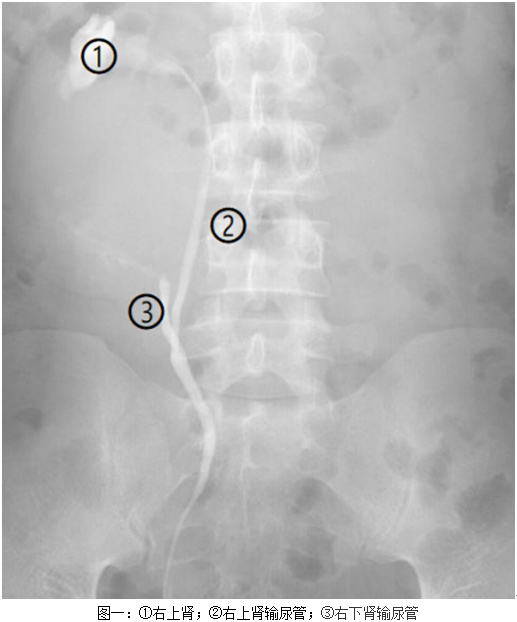

近日,我科收治一男性患者,该病人于外院诊断为肾囊肿,拟入我科行手术治疗,要求刘川教授亲自主刀。患者入院后,我院CT检查提示马蹄肾、双